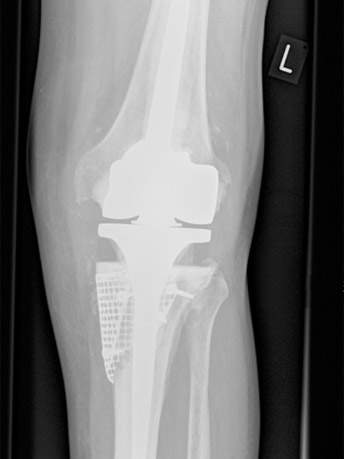

X-ray showing the same patient after revision surgery using a rotating hinge knee replacement and bone grating to the tibia contained with metal mesh (AP view).